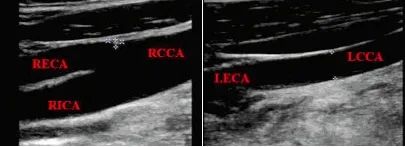

此時進行頸部血管超聲檢查,發(fā)現(xiàn):雙側CCA管徑不對稱,RCCA管徑9.5 mm,向上分出RECA后,延續(xù)為RICA;LCCA管徑4.5 mm,向上未見分叉,直接延續(xù)為LECA,LICA管腔未顯影,如下圖,頸部血管超聲提示LICA先天未發(fā)育。